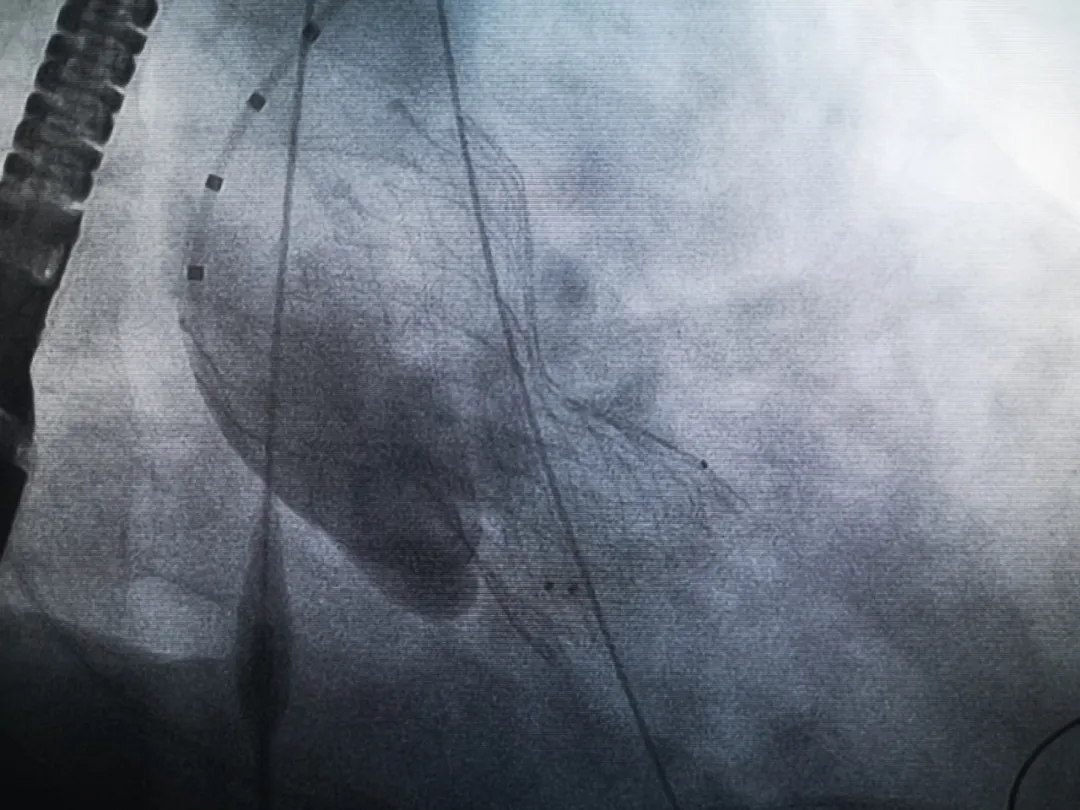

王子的手術(shù)被安排在周五。術(shù)前一天,TAVR團隊再次碰頭討論,從麻醉中血壓控制、球囊擴張、瓣膜釋放,到各種可能突發(fā)狀況的應(yīng)對,都提前制定了方案。尤其是瓣膜鈣化極為嚴重,對于擴張球囊型號的選擇、擴張的力度以及瓣膜植入后瓣周漏的發(fā)生預(yù)測,都具有很大挑戰(zhàn)。然而,如果沒有這些挑戰(zhàn),他又何必選擇我們呢!

手術(shù)過程緊張而有序,心臟沒有停跳,也沒有太大的血壓波動;球囊擴張的恰到好處,瓣膜釋放之后超聲醫(yī)生的評估是至關(guān)重要的,因為我們提前就準(zhǔn)備了后擴張,也準(zhǔn)備了瓣中瓣,甚至還準(zhǔn)備了瓣周漏封堵。所幸的是,超聲診療中心劉夢梅醫(yī)生說:沒有返流、沒有瓣周漏,瓣膜形態(tài)良好,跨瓣壓差約17mmHg(相較于術(shù)前的87mmHg還是可以接受的)。瓣膜置入的成功并不是慶祝的時候,從戰(zhàn)場撤退仍然需要謹慎。由于王子特別胖,腹股溝區(qū)脂肪尤為肥厚,在股動脈插管拔除、確認搏動正常之后,便逐層縫合。同時為了美觀、縫合之后不至于鼓個包出來,我們又仔細剪除了部分脂肪。術(shù)后次日,王子便可以下床活動了。